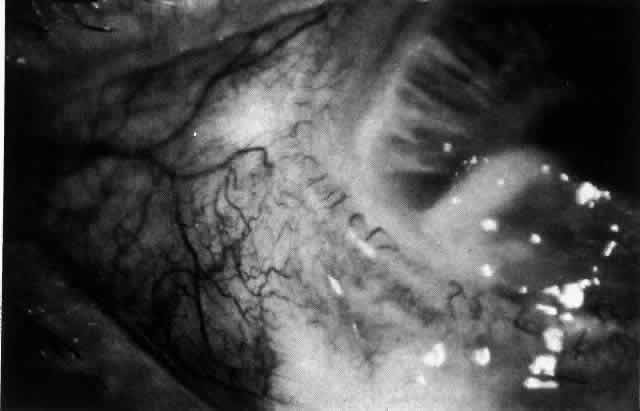

The redness of simple episcleritis may be intense, varying from a fiery-red or a brick-red discoloration to a mild red flush, but it does not have the bluish tinge that is seen in scleritis. The distribution is usually sectorial but can involve the whole anterior segment of the globe. The episcleral vessels are engorged but retain their normal radial position and architecture (Figs. 13 and 14; Color Plate 1A). In simple episcleritis, there is a diffuse edema of the episcleral tissues. These tissues are sometimes infiltrated with gray deposits that appear yellow in red-free light. Surprisingly, the eye is rarely tender to the touch.

Fig. 13. Infiltration of the episclera in which the superficial episcleral vessels show maximal congestion. Conjunctival vessels are slightly congested, as is the deep episcleral plexus, whose irregular criss-cross pattern can be seen deep to the radially arranged superficial episcleral plexus.

Fig. 14. Diffuse inflammation. Superficial vessels are maximally engorged and retain their radial pattern and architecture. (See Figures 27 and 34.) (Watson PG: Connective tissue disorders and the eye. In: Recent Advances in Ophthalmology, Vol 5, pp 214–277. London, Churchill-Livingstone, 1975)